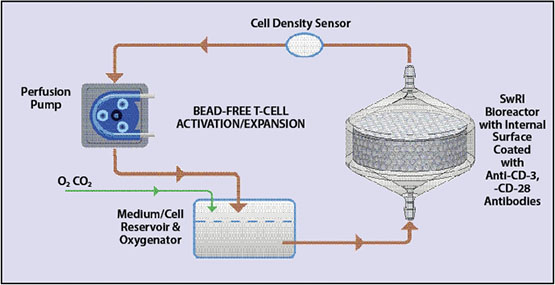

SwRI’s bioreactor facilitates pump-driven perfusion flow-based cell cultures. Perfusion technology mimics the human circulatory system to provide nutrition and oxygen to cells to support growth. Over long periods, a week or two, these systems culture cells continuously, providing the cells with fresh media and removing waste, similar to the circulation system in our bodies.

We are developing a turnkey, standalone system about the size of a minifridge as the demonstration perfusion unit. This includes a temperature-controlled incubator and a pump — like a heart — to deliver media to the cells inside the bioreactor. An oxygenator functions like our lungs, refreshing the oxygen concentration and removing carbon dioxide based on the “breathing rate” of the cells. We conducted computational fluid dynamics simulations to demonstrate the media perfusion flow profile across the bioreactor. We enhanced the system with a programmable controller to automate the nutrition and oxygen delivery for cell propagation. And we are integrating the bioreactor with tubing, a media storage bag and a waste collection bag to form a closed, single-use package that can be installed into the perfusion unit.

Current cell manufacturing is a complex, labor-intensive process that can cost up to $500,000 for a single treatment of personalized T-cell immunotherapy. These “open” processes require a high-cost Class 100 cleanroom environment. For CAR T-cells, magnetic microbeads are used for T-cell purification, activation and expansion. As the cells are harvested, the beads must be separated from the cells. However, it is difficult to completely remove the beads from the cells, so they often are infused into a patient along with T-cells, resulting in a potential safety issue. In contrast, our bioreactor does not require microbeads in T-cell manufacturing.

SwRI’s bead-free perfusion-based system offers closed-loop, automated T-cell activation, transduction and expansion in comparison to the complex, labor-intensive processes typically requiring Class 100 cleanrooms.